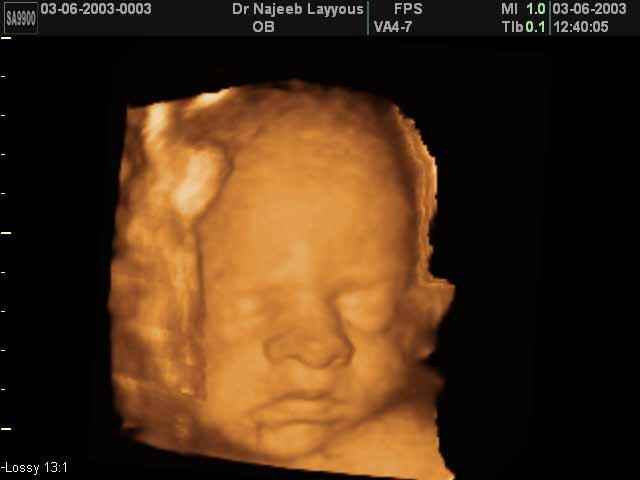

- 3D Fetal Profile Ultrasound Scan Photos

3D Fetal Face Ultrasound Scan Photos | Dr N Layyous